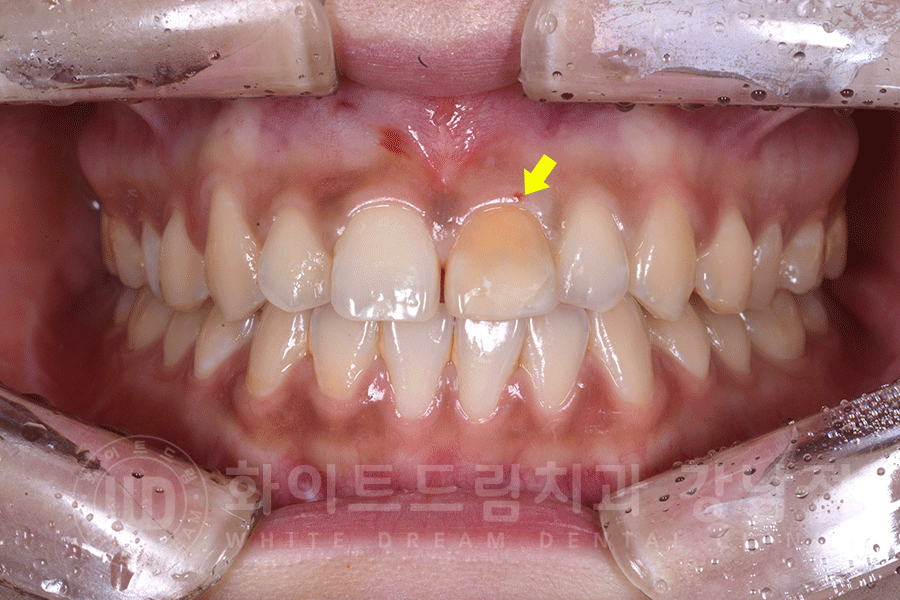

환자분의 구내 사진입니다.

앞니 변색으로 강남역 주변 치과를 찾아주신 환자분의 초기 구내 사진입니다.

신경치료를 받은 치아는 시간이 지나면서 점점 치아색이 변색됩니다.

환자분처럼 눈에 잘 보이는 앞니가 변색이 되면,

다들 내 앞니만 보는 것 같고, 자신감이 떨어지면서 소극적으로 변하게 되는데요.